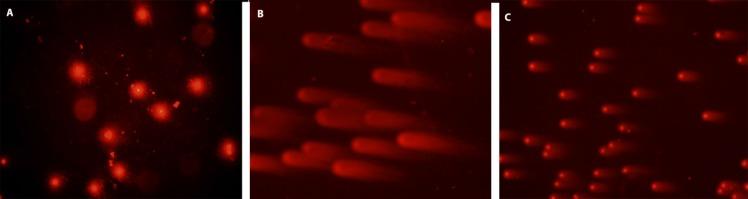

The present study investigates the antioxidant, anticancer, anticholinesterase, anti-genotoxic activities and phenolic contents of flower, fruit and seed methanol extracts of AUCHER. The amounts of protocatechuic acid, catechin, caffeic acid and syringic acid in methanol extracts were determined by HPLC. Total phenolic content of seed extract was found more than fruit and flower extracts. The DPPH free radical scavenging activity of flower and seed methanol extracts showed close activity versus BHT as control. Among three extracts of only flower methanol extract was exhibited considerable cytotoxic activities against to HeLa and NRK-52E cell lines. Moreover, seed methanol extract showed both acetyl and butyrl-cholinesterase inhibitory activity. The highest anti-genotoxic effects were seen 25 and 50 μg/mL concentrations. In this study, the extracts showed a strong antioxidant and anti-genotoxic effect. The seed extract was more efficient- than extracts of fruit and flowers. Our results suggest that the antioxidant and anti-genotoxic effects of extracts depend on their phenolic contents. Further studies should evaluate the and the benefits of seed methanol extracts.

本研究调查了奥氏蔷薇花、果实和种子甲醇提取物的抗氧化、抗癌、抗胆碱酯酶、抗基因毒性活性及酚类成分。通过高效液相色谱法测定甲醇提取物中原儿茶酸、儿茶素、咖啡酸和丁香酸的含量。发现种子提取物的总酚含量高于果实和花提取物。花和种子甲醇提取物的DPPH自由基清除活性与作为对照的丁基羟基甲苯表现出相近的活性。在三种提取物中,只有花甲醇提取物对HeLa和NRK-52E细胞系表现出显著的细胞毒性活性。此外,种子甲醇提取物表现出乙酰胆碱酯酶和丁酰胆碱酯酶抑制活性。在25和50μg/mL浓度下观察到最高的抗基因毒性作用。在本研究中,提取物表现出强大的抗氧化和抗基因毒性作用。种子提取物比果实和花提取物更有效。我们的结果表明,提取物的抗氧化和抗基因毒性作用取决于其酚类成分。进一步的研究应评估种子甲醇提取物的……及其益处。